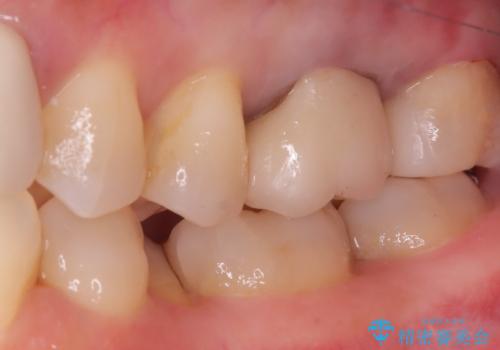

- 主訴:昔入れた銀の詰め物を白い物に替えて金属を無くしたい。

審美性、適合性の観点からセラミックインレーでのやり替えとなりました。

保険適用のメタルインレーを除去した際、下に広がっているカリエスも除去し形成印象を行いました。

セラミックインレーセット時はラバーダム防湿を行っています。